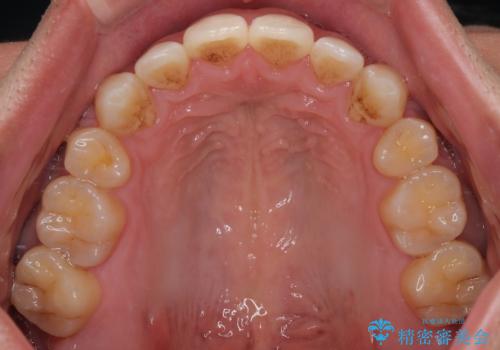

- 前歯のデコボコ(叢生)と、少し前に出た口元を気にされて来院された患者さまです。

診査の結果、上下顎ともに歯が並ぶスペースが不足しており、上下の前歯が噛み合わない**オープンバイト(開咬)**の状態でした。

歯をすべて並べようとすると口元がさらに前に出てしまうため、上下左右の第一小臼歯を抜歯してスペースを確保し、デコボコと突出感の両方を改善する治療計画を立てました。